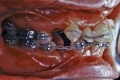

| 初診時

| マルチブラケット終了時